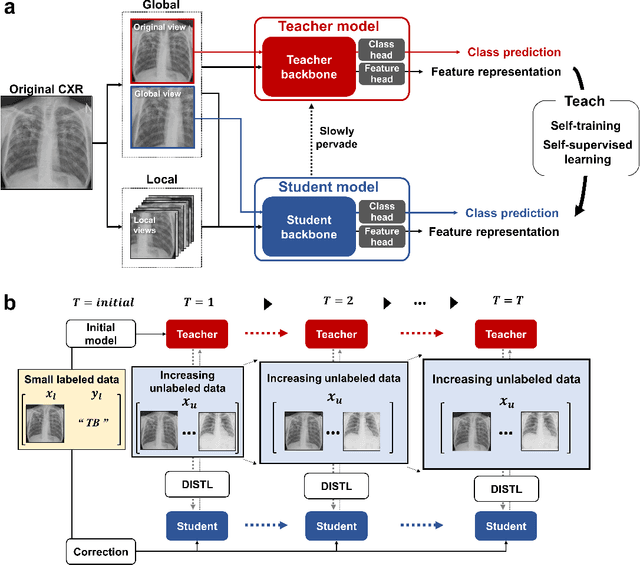

Abstract:Although deep learning-based computer-aided diagnosis systems have recently achieved expert-level performance, developing a robust deep learning model requires large, high-quality data with manual annotation, which is expensive to obtain. This situation poses the problem that the chest x-rays collected annually in hospitals cannot be used due to the lack of manual labeling by experts, especially in deprived areas. To address this, here we present a novel deep learning framework that uses knowledge distillation through self-supervised learning and self-training, which shows that the performance of the original model trained with a small number of labels can be gradually improved with more unlabeled data. Experimental results show that the proposed framework maintains impressive robustness against a real-world environment and has general applicability to several diagnostic tasks such as tuberculosis, pneumothorax, and COVID-19. Notably, we demonstrated that our model performs even better than those trained with the same amount of labeled data. The proposed framework has a great potential for medical imaging, where plenty of data is accumulated every year, but ground truth annotations are expensive to obtain.